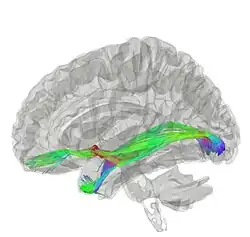

La commissure antérieure, appelée également la commissure blanche antérieure ou encore la précommissure (en latin : commissura anterior), est une commissure inter-hémisphérique qui croise transversalement la paroi antérieure du troisième ventricule[1]. C'est un faisceau nerveux de substance blanche (un paquet d'axones) qui relie les deux lobes temporaux des hémisphères cérébraux à travers la ligne médiane, et il se trouve en avant des colonnes du fornix (les piliers antérieurs trigone du cerveau). Chez la plupart des mammifères existants, la grande majorité des fibres reliant les deux hémisphères traversent le corps calleux, qui est plus de 10 fois plus grand que la commissure antérieure, et d'autres voies de communication passent par la commissure de l'hippocampe ou indirectement, via des connexions sous-corticales. Néanmoins, la commissure antérieure est une voie importante qui peut être distinguée clairement dans les cerveaux de tous les mammifères.

Les fibres de la commissure antérieure peuvent être tracées latéralement et postérieurement de chaque côté au-dessous du corps strié vers la substance du lobe temporal.

Le fonctionnement de la commissure antérieure demeure pas encore élucidé complètement. Les chercheurs l'ont impliqué dans plusieurs fonctions allant de la perception des couleurs à l'attention. Une de ces études a soutenu la perception des couleurs dans l'agénésie du corps calleux (Ceux nés sans corps calleux; Barr & Corballis, 2002)[6]. D'autres études se sont appuyées sur cela pour impliquer que la commissure antérieure peut être une voie compensatoire chez les personnes sans corps calleux, présentant des techniques d'imagerie diffusion pour mieux élucider la commissure antérieure et comment elle pourrait être impliquée dans diverses fonctions (Winter & Franz, 2014).